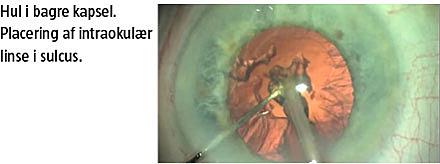

I forbindelse med operationerne er der risiko for en række komplikationer herunder kapselbrist, fremfald af glaslegemet, læsion eller fremfald af regnbuehinden gennem incisionen, tab af linsekernen ned i glaslegemet, løshed af linsens ophængsapparat, peroperativ trykstigning og blødning.

Resultatet af den kliniske høring med en tolkning og årsagsforklaring af komplikationerne er vist i Tabel 1. Der var i alt syv (0,4%) rupturer af den bagerste kapsel. Hos patient nr. 6 var den beskrevne kapselbrist og korpustabet uundgåeligt pga. en præoperativt tilstedeværende defekt i bagerste kapsel. Der var to øjne med løshed af linsens ophængningsapparat fra operationens begyndelse. Tre komplikationer (1, 3 og 9) var uden særligt mønster. To komplikationer (10 og 11) skyldtes mangelfuld kontrol med intraokulært placerede skarpe instrumenter. Den samlede komplikationsfrekvensen var 9/1.440 (0,6%) blandt erfarne kirurger og 5/131 (3,8%) blandt læger under kirurgisk indlæring. I sidstnævnte gruppe kunne komplikation nummer 7 tilskrives en fejlvisitation af en teknisk set meget krævende operation, mens tre komplikationer var såkaldte »billetklip« i den bagerste linsekapsel pga. for megen ultralydenergi for tæt på linsekapslen ved fjernelse af linsekernen. Trods komplikationer opnåede samtlige patienter et bedre syn som følge af operationen.